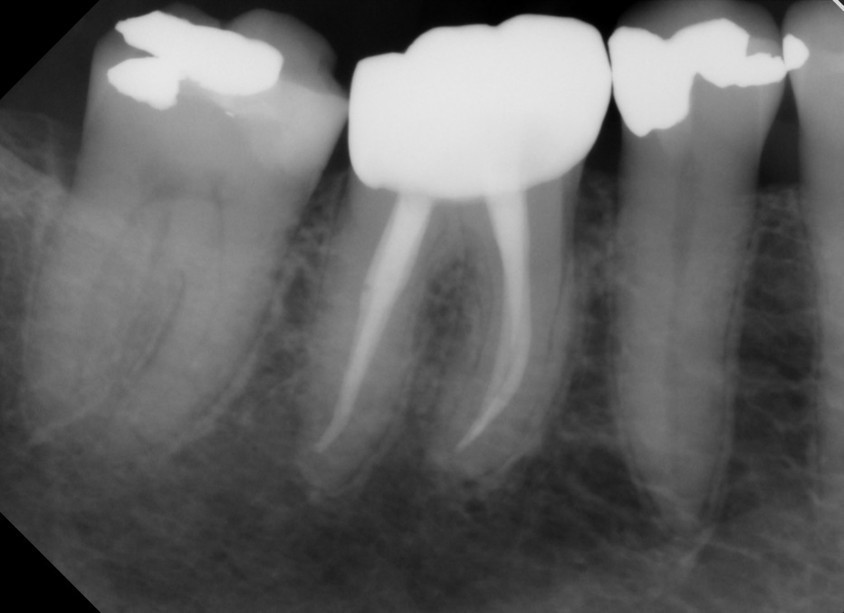

- Hohe Röntgenopazität: Mit einem Wert von ca. 9,5 bis 10,5 mm Al ist die Füllung auf Röntgenaufnahmen sehr gut sichtbar und leicht zu beurteilen.